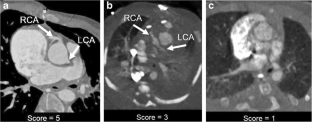

Two hundred eleven high-pitch ECG-triggered studies from April 2014 to November 2017 were reviewed by two pediatric cardiac imagers in this retrospective study. Patient age, gender, BSA, average heart rate, heart rate variability and use of general anesthesia were recorded as well as dose–length product (DLP) and volumetric CT dose index (CTDIvol). We assessed the coronary artery score using a 5-point scale, with score of ≥3 considered of diagnostic quality. We performed multivariate statistical analysis including logistic regression to analyze effects of heart rate and BSA.

Patient age range was 1 day to 19 years (median age 3 years). Heart rate range was 49–188 beats per minute (bpm; median 122 bpm) and BSA range was 0.15–2.07 m2 (median 0.53 m2). The origin and proximal coronary arteries were confidently seen (score ≥3) in 61% of studies in this cohort. Coronary artery visualization scores further increased with increased BSA (P<0.002) and with decreased heart rate (P<0.001). At heart rates <100 bpm or in patients with BSA>0.58, adequate coronary artery visualization was present 72% of the time.